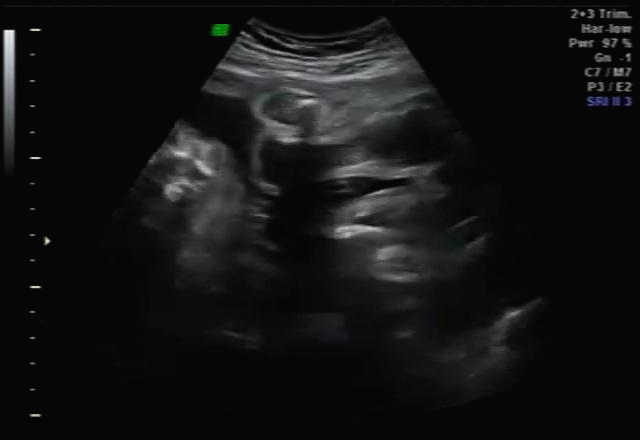

한 달 뒤인 17차 때 다시 사설로 가서 초음파 검사를 받았는데 검사해주시는 분 께서 한참을 보시더라고요~ 그러면서 어떻게 보면 딸 같다고 하셔서... 응? 100프로 아들이라 해서... 다 아들껄로 준비하고 있는데.. 무슨 소리지? 하고 다시 한번 봐달라고 하니 아들이라 하시면서 위에 초음파를 보여주셨어요!

한데 기분이 참 찝찝했어요~ 뭔가 숨기고 있는 듯한.. 정확하지 않는 듯한 느낌 ㅋㅋㅋ... 그래서 임신 17주 차부터 아이 용품 구매하는 걸 중단하고 병원에서 20주 차 정밀 초음파 검사를 기다려 보기로... 가족도 다 아들로 알고 있고 벌써 아들 꺼 처럼 보이는 용품들로 준비했기 때문에 성별 반전이 없기를 기대했어요 ㅠㅠ